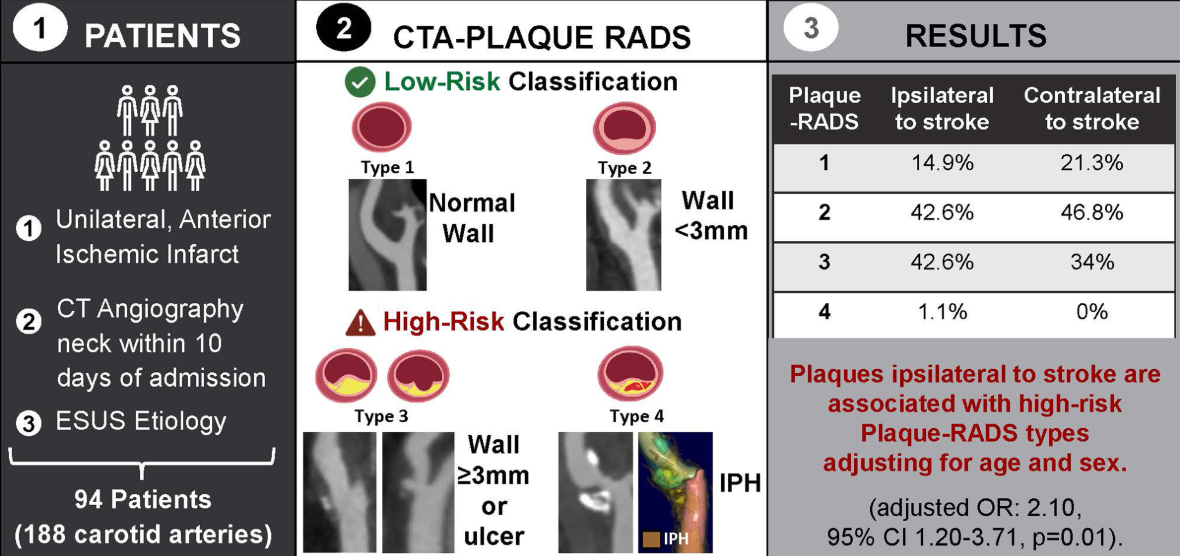

Prevalence of High-Risk CTA-Based Carotid Plaque-RADS Subtypes in Patients With Embolic Stroke of Undetermined Source (Jan 2025)

We apply a modified CT-based Carotid Plaque-RADS framework to an ESUS cohort and show high-risk Carotid Plaque-RADS subtypes are more prevalent on the ipsilateral side of stroke.